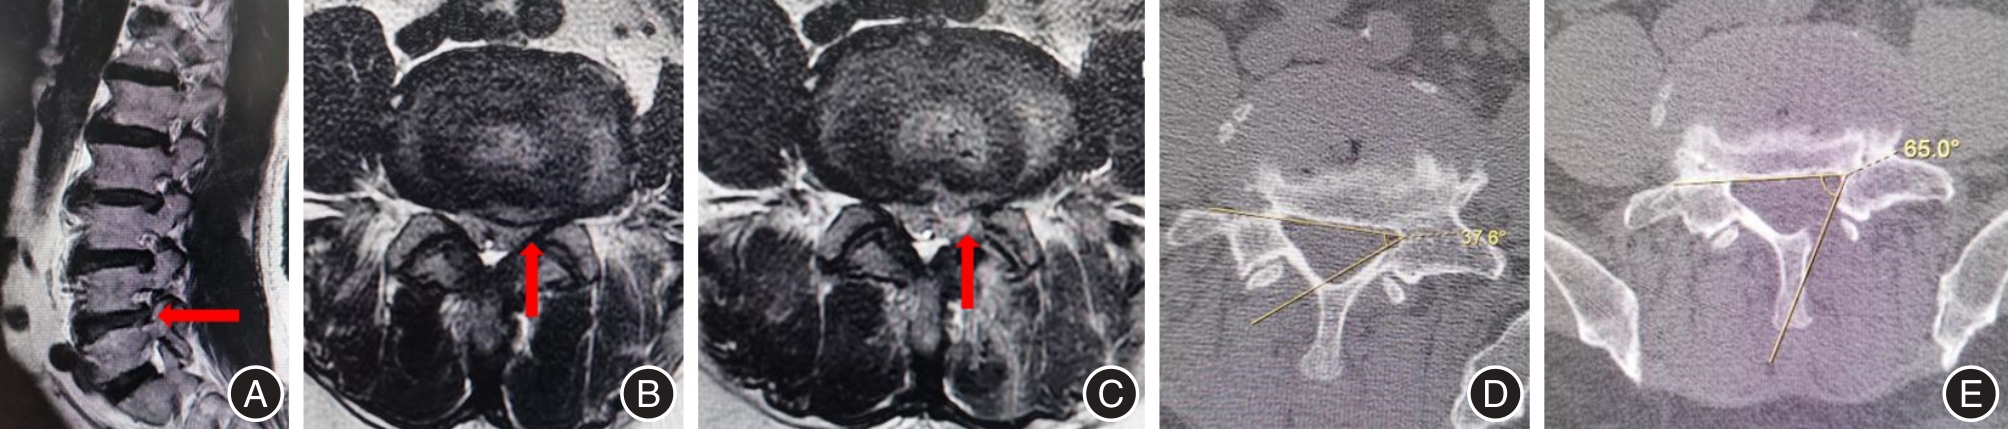

| LRA | 术前 | 32.50 ± 9.30 | 34.23 ± 7.86 | -1.73(-6.63 ~ 3.17) | -0.710 | 0.481 |

| 术后3 d | 69.86 ± 5.22* | 72.84 ± 6.07* | -2.98(-6.20 ~ 0.24) | -1.861 | 0.069 |